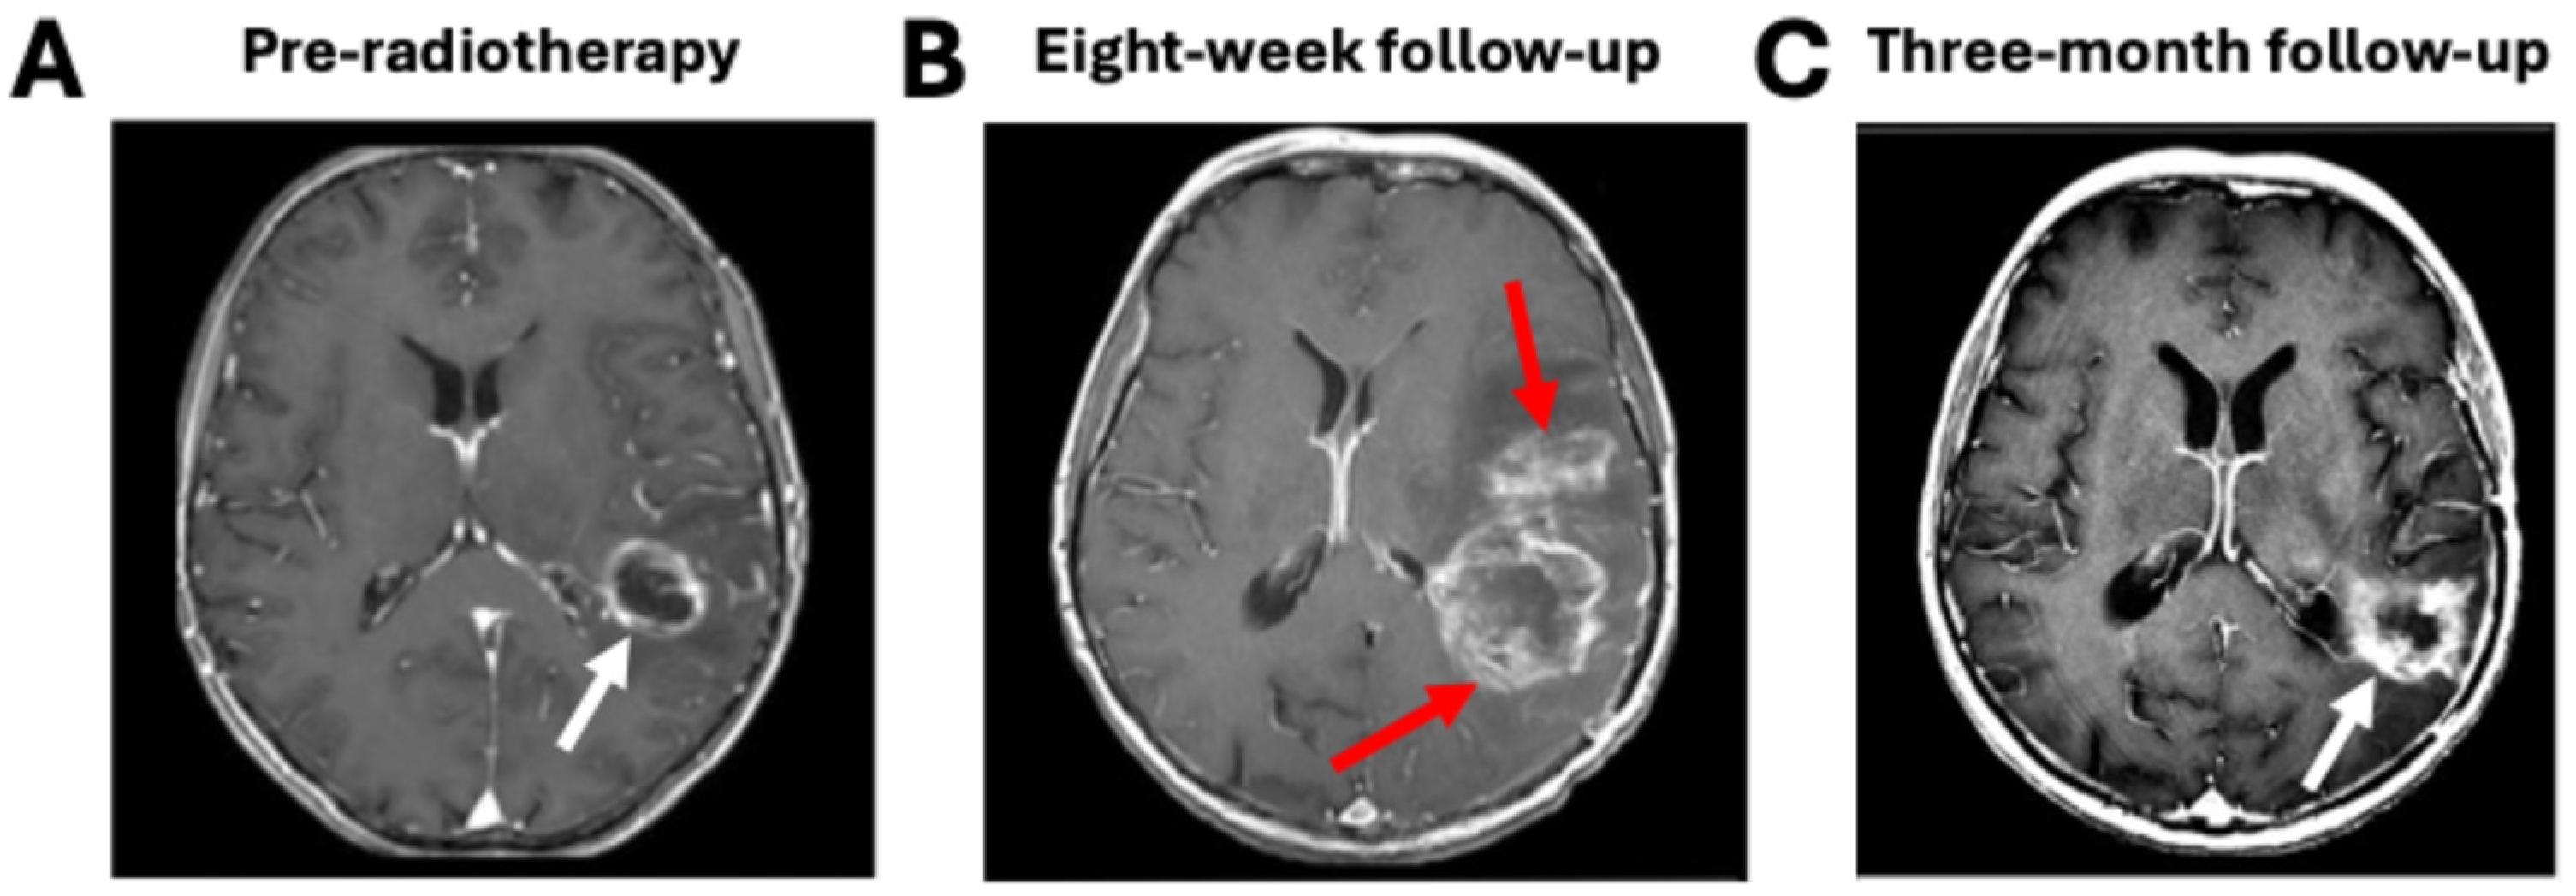

Response assessment poses another set of challenges common to both glioma and brain metastasis treatment. Although tumor progression is defined as an increase in the size of enhancing lesions, increased enhancement can occur for reasons related to treatment rather than disease. Pseudoprogression is a phenomenon that occurs in approximately 10–30% of patients whereby enhancing lesions develop within the radiation field, sometimes with corresponding clinical symptoms, and then subsequently decrease in size or disappear without intervention (Figure 2) [32]. MGMT promoter methylation predicts a greater chance of pseudoprogression [33]. Pseudoprogression is thought to be related to enhanced vessel permeability resulting from the radiation. Radiation necrosis is another, more severe, treatment effect yielding an increased size of enhancing lesions that involves vascular injury and glial and white matter damage due to the radiation [34]. Radiation necrosis occurs in approximately 5–25% of brain metastasis patients following stereotactic radiosurgery and can be symptomatic and progressive [35]. Because of pseudoprogression, the RANO criteria for gliomas are generally not applied within the first three months after treatment, and the RANO-BM criteria for brain metastases to declare progression can also be delayed [23,25]. Furthermore, changes in macroscopic tumor size are frequently delayed relative to microscopic tumor changes indicative of a response. Preclinical studies have shown that the tumor response to radiation at a cellular level occurs much earlier than changes in tumor size, including changes in metabolism or the onset of apoptosis and necrosis [36]. Clinical studies have demonstrated a correlation between early changes in physiologically sensitive imaging sequences and patient outcomes that are not reflected by macroscopic tumor changes at the same timepoints [37,38,39,40].

Figure 2.

Pseudoprogression mimics true tumor progression. (A) A glioblastoma patient immediately pre-radiotherapy shows an enhancing left frontoparietal lesion (white arrow). (B) At the eight-week follow-up timepoint, immediately post-radiotherapy, new areas of enhancement are visible (red arrows). (C) At the three-month follow-up timepoint, the new regions of enhancement have spontaneously disappeared, and the only lesion visible is at the original tumor site (white arrow). Figure was adapted from Carrete et al. under a Creative Commons License [41].